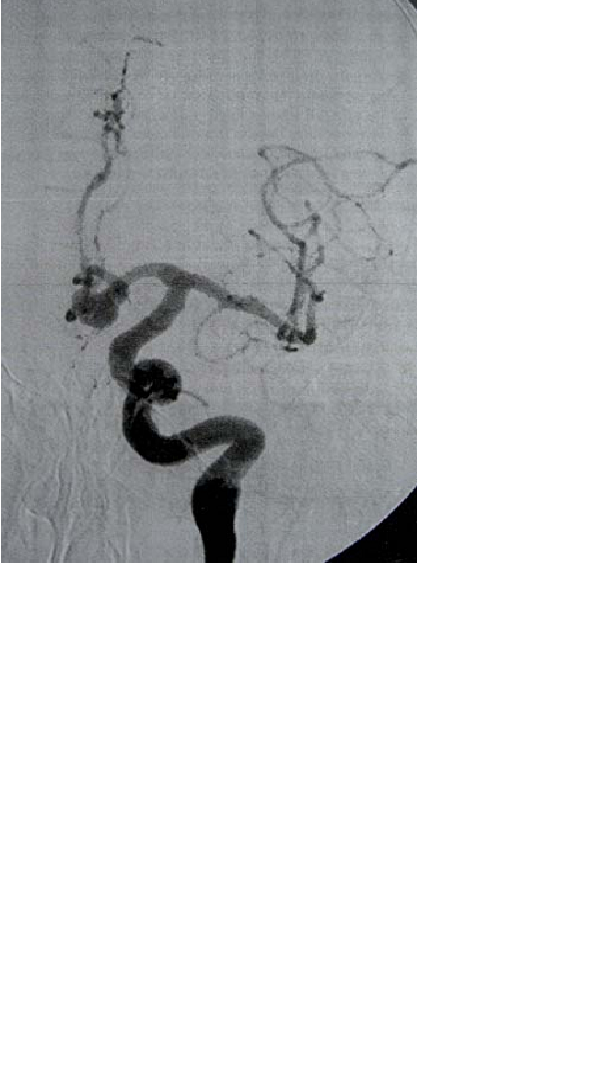

Skenario: Seorang laki-laki usia 67 tahun dengan riwayat diabetes mellitus dan hipertensi dibawa ke bagian gawat darurat dengan lengan kanan lemah dan mati rasa. Ternyata dia memiliki stenosis

>90% pada arteri karotid interna kiri dan difusi MRI terbatas pada bagian-bagian otak yang dipasok dari arteri serebral medial kiri. Pasien memilih melanjutkan bedah untuk stenosis karotidnya tetapi

ternyata mengalami bifurkasi arteri karotid riding yang tinggi.